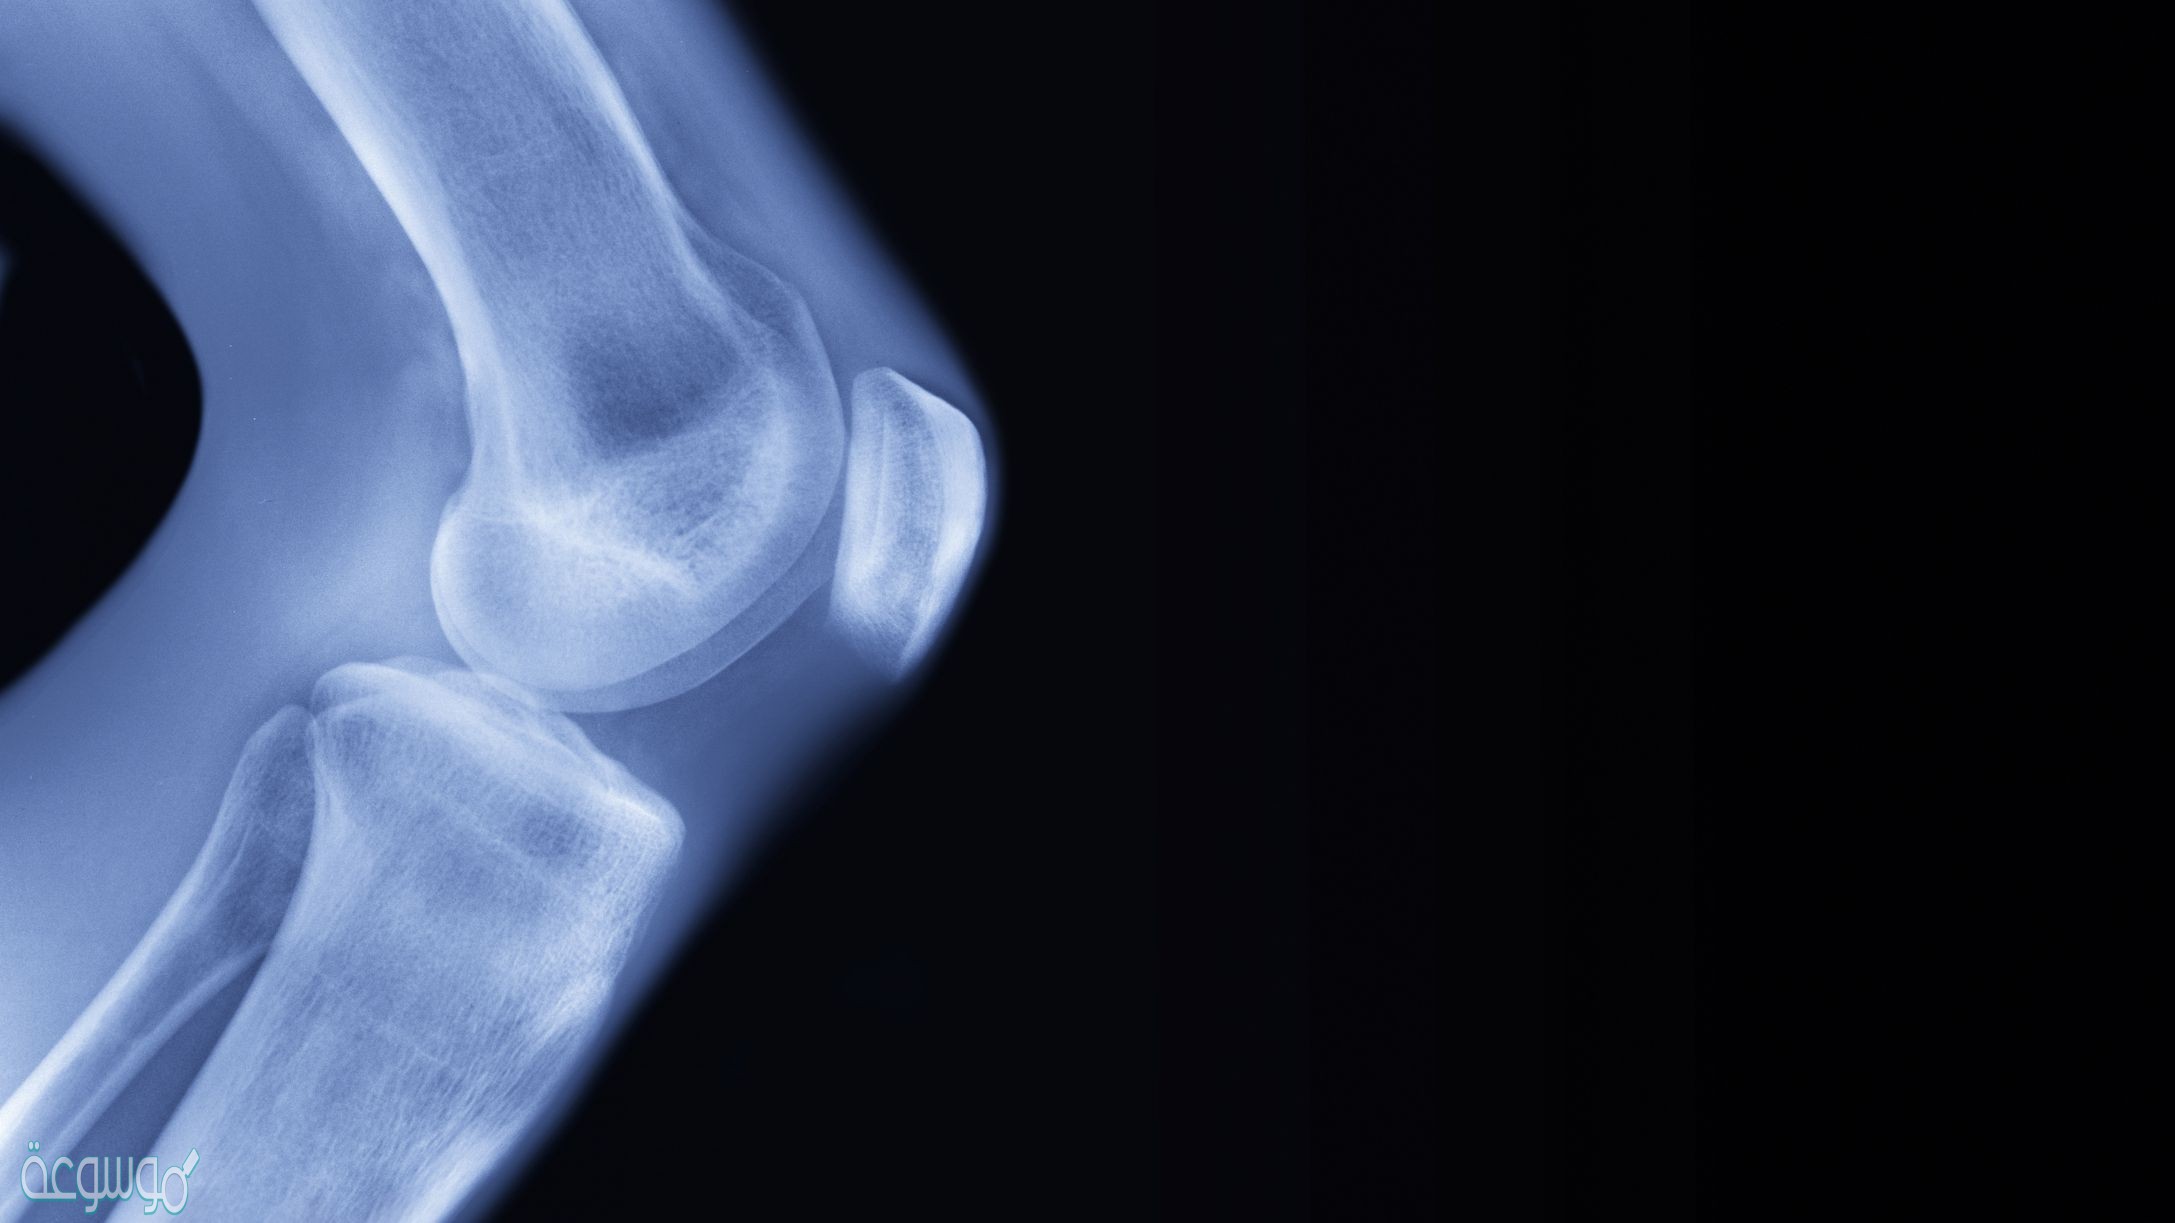

المفصل هو نقطة التقاء عظمتين أو أكثر، حيث هناك ثلاثة أنواع رئيسية من المفاصل، وهم: ليفي (غير متحرك)، غضروفي (متحرك جزئيًا) ومفصل زليلي (متحرك بحرية).

يمكن تصنيف المفاصل الزليليّة بدورها إلى ست مجموعات وفقًا لنوع الحركة التي تسمح بها: مفصل مستوي، ومفصل كروي ومقبس، ومفصل مفصلي، ومفصل محوري، ومفصل لقمي ومفصل سرج.

المفاصل هي المكان الذي تلتقي فيه العظام أو تتصل بها، والأربطة عبارة عن عصابات قصيرة من النسيج الضام الليفي القاسي والتي تعمل على ربط عظم بأخرى وتشكيل المفصل، وأما الأوتار مصنوعة من نسيج مرن وتلعب أيضًا دورًا رئيسيًا في عمل المفاصل، حيث يربطون العضلات بالعظام، ومن خلال التالي الإجابة على التساؤل التالي:

- الإجابة/ ترتبط العظام مع المفاصل بالأربطة ويوجد عدد من الاربطة لتثبت العظام في المفصل.